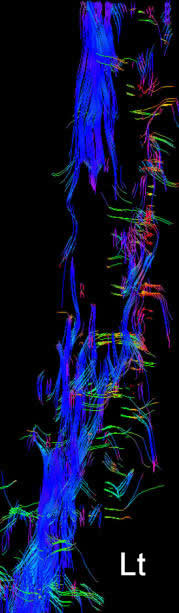

Fibertraking of the spinal cord around the lesion in anterior first, left second, posterior third and the last is right projections showing the fibers more concentrated in the left side, despite the fact the patient has weak left foot.

Intraoperative MRI axial views showing that the spinal cord mass was mainly in the left side supporting the fibertraking data.